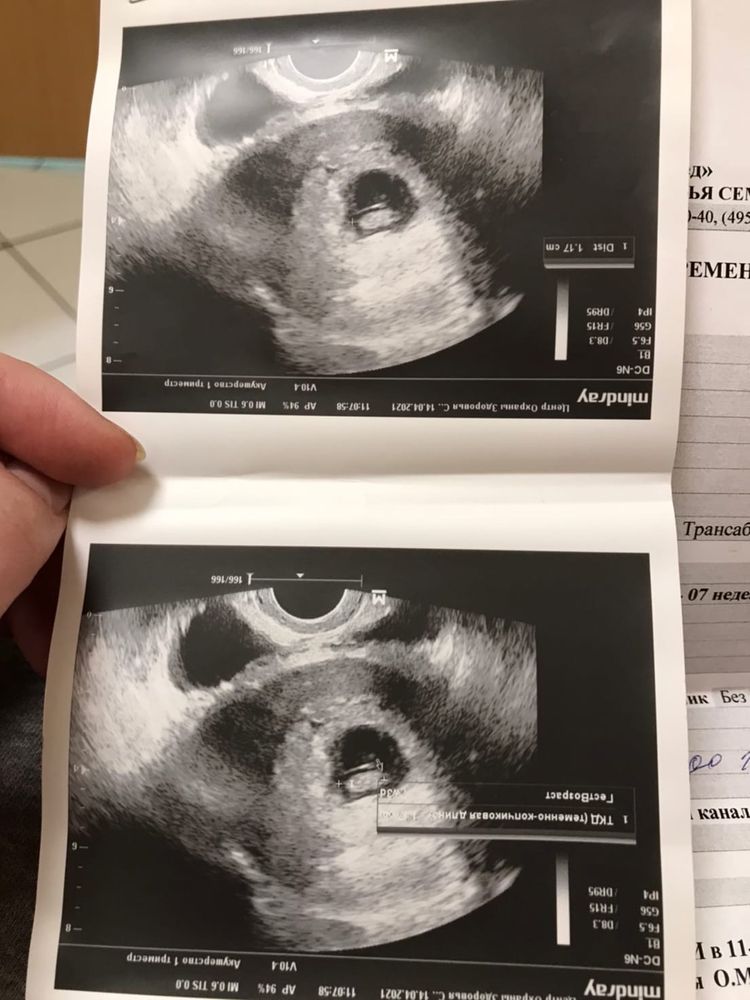

1 триместр. Ни дня токсикоза, пару раз давление немного поднималось.. Откуда то взялась отслойка 2 см. все самоликвидировалось к сл